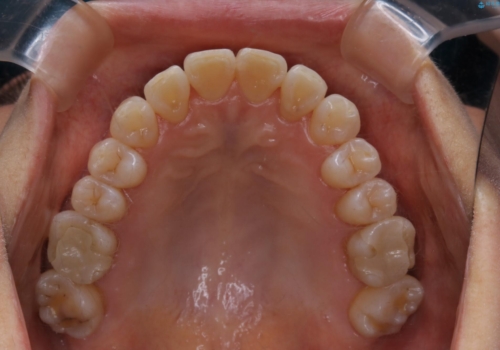

前歯の反対咬合、奥に引っ込んでしまっている歯をインビザラインで治療する

- インビザラインでの治療を希望した患者様です。

上の前歯の反対咬合があり、治療の途中で下の前歯を乗り越える必要があります。

前歯を乗り越える治療はワイヤーの方が有利ではありますが、インビザライン単独でも行うことができます。